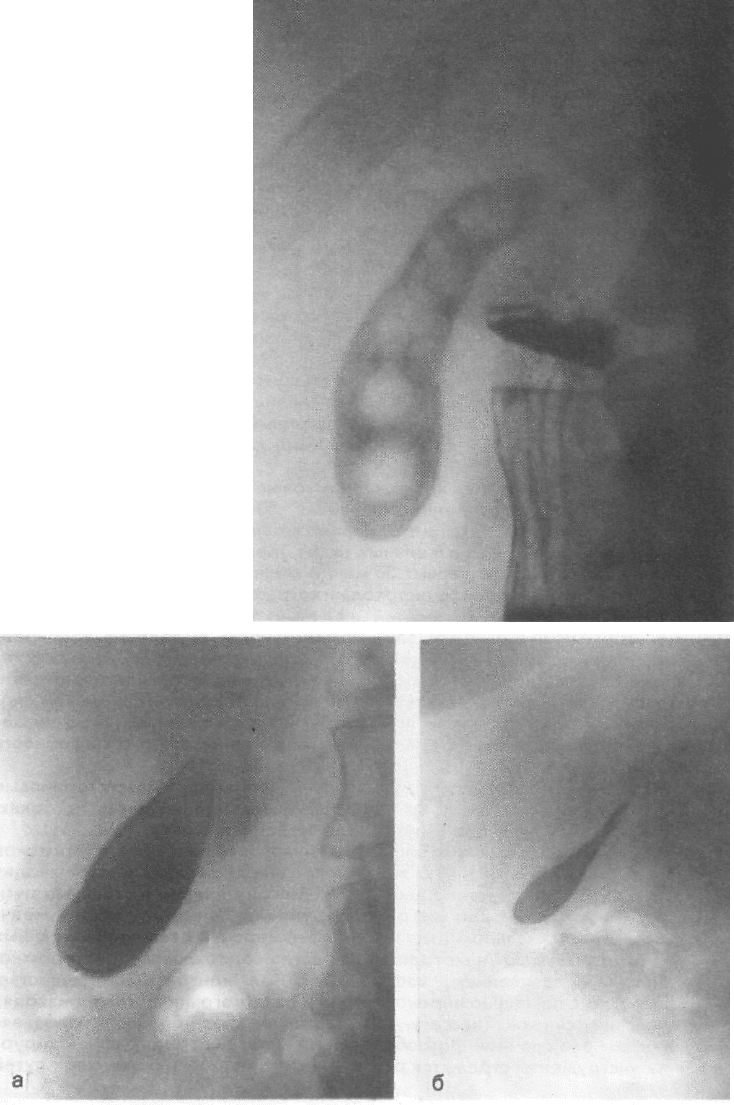

Исследование желчных путей

Исследование желчных путей 112 фото